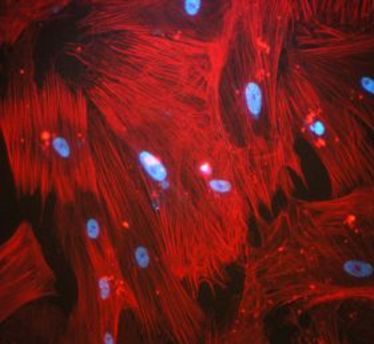

AG Sorokin mit neuer Website

AG Sorokin mit neuer Website